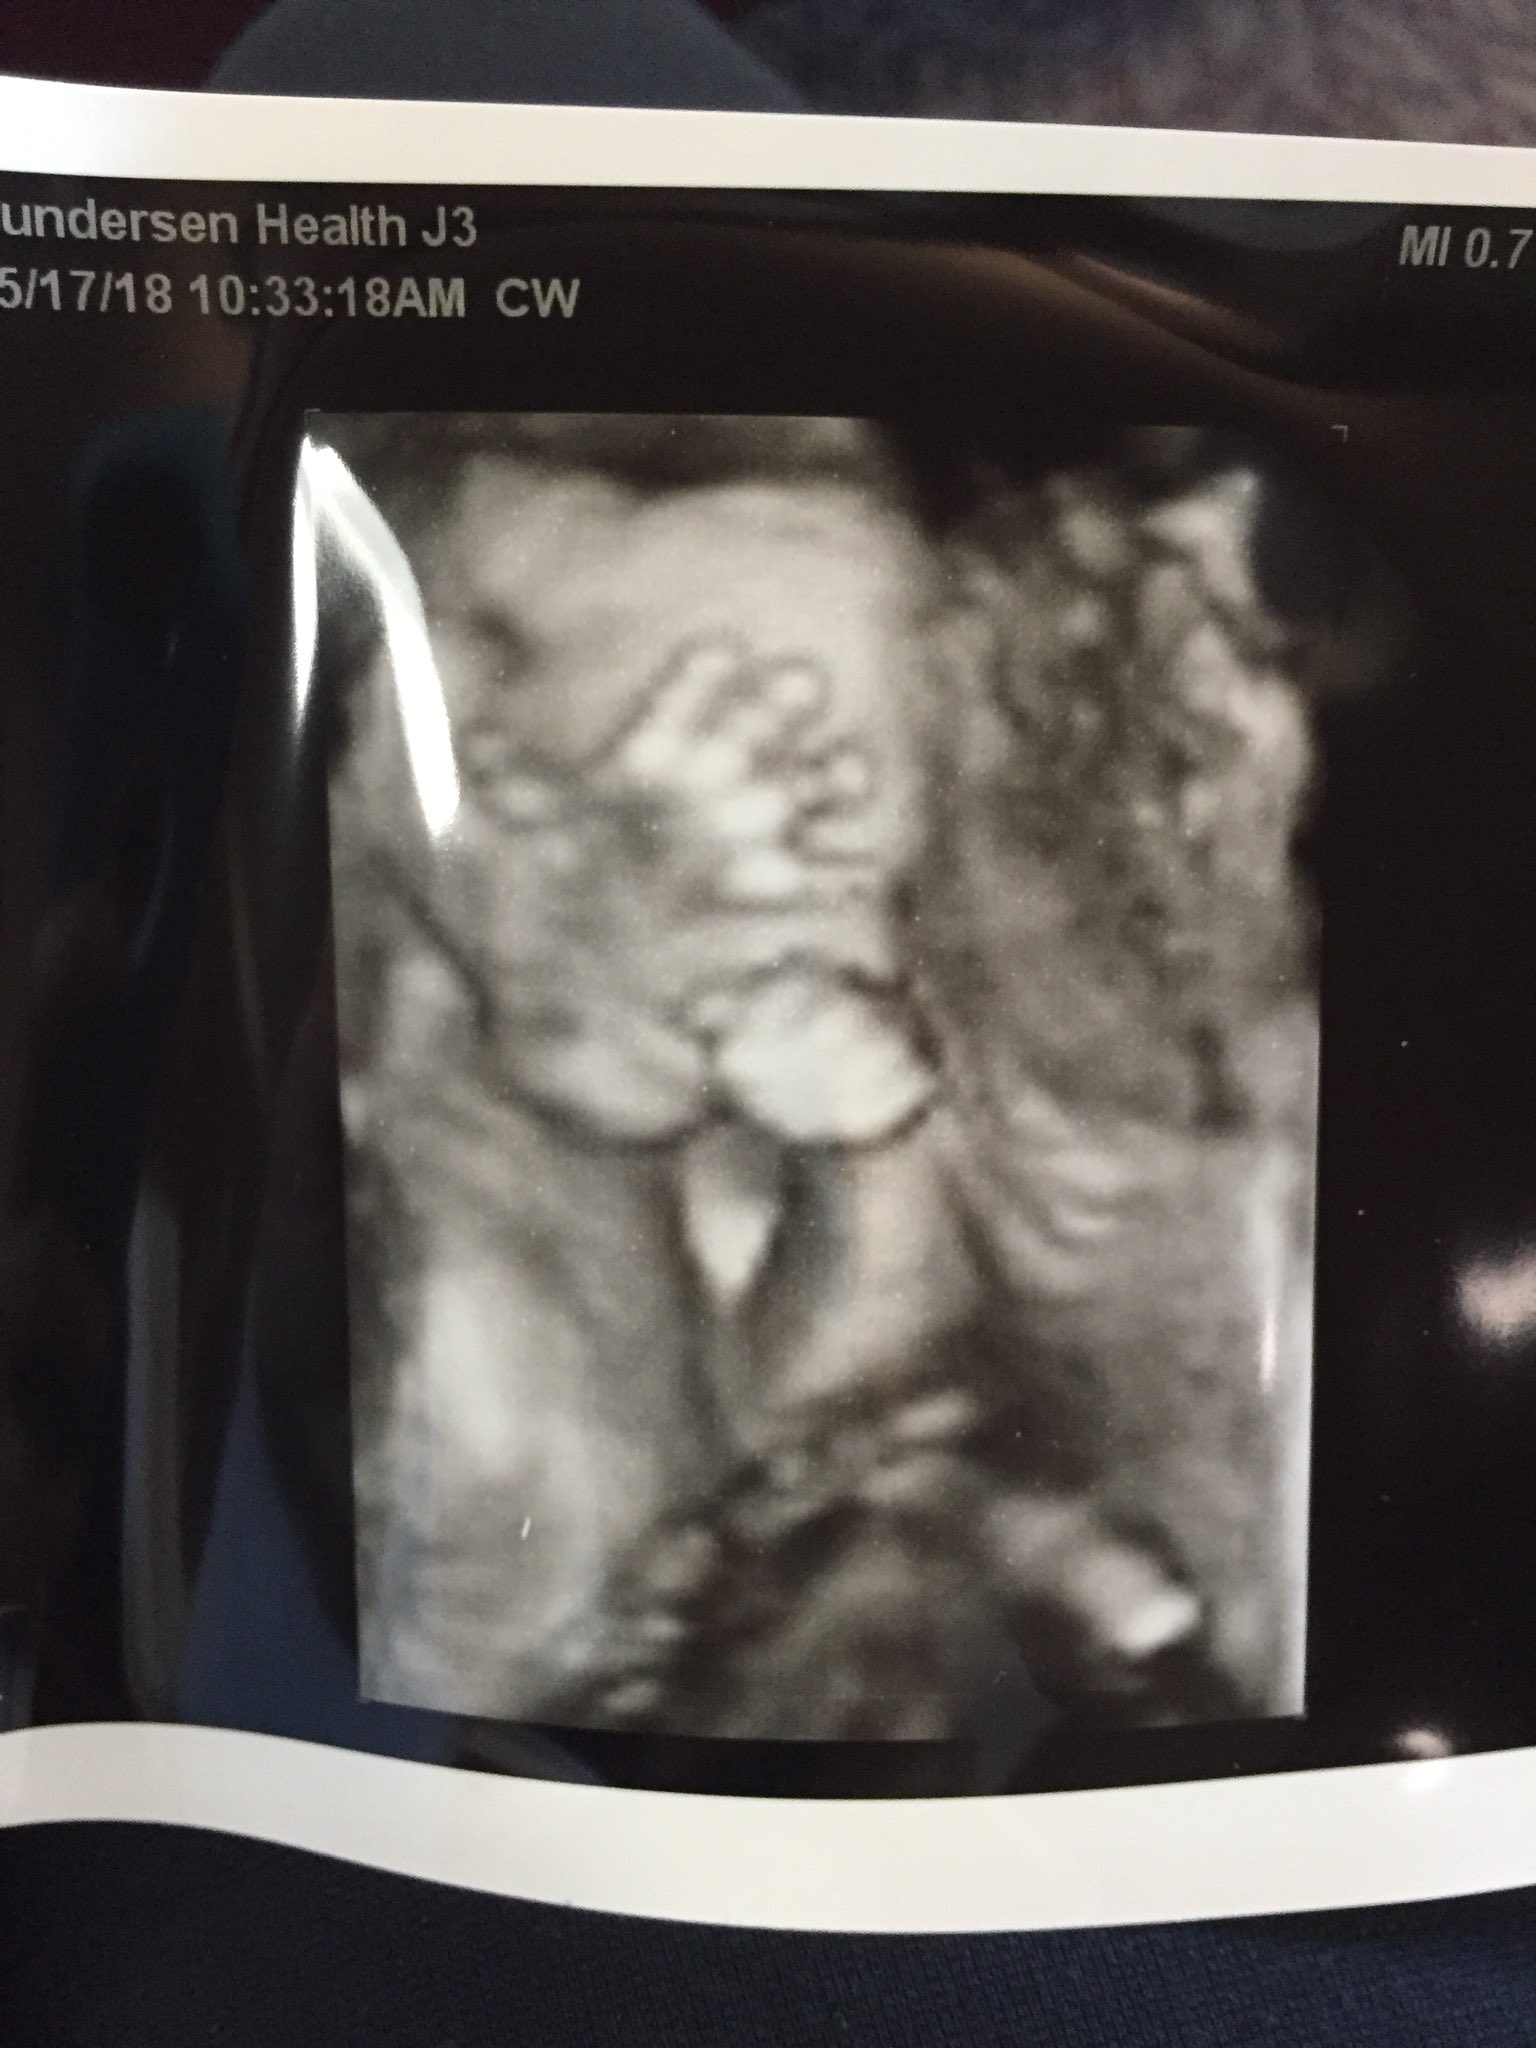

hair on ultrasound 20 weeks

She told me the little white lines on the head were hair. Hair on ultrasound 20 weeks Sunday July 17 2022 Edit.

I was so surprised that we could see it on a regular ultrasound.

The soft spot that your baby has at birth exists during pregnancy too and you might actually see this gap in the skull during your first anatomy scan. Unfortunately 3D4D ultrasound technology cannot see any hair on the baby however standard 2d black and white ultrasound can usually pick up strands of hair. Yes at our last ultrasound at like 32 weeks the tech commented that baby had a headful of hair.

Is this hair on my babys head at 20 week ultrasound. Around 20 weeks fine downy hair starts to sprout from these follicles on the eyebrows upper lip and chin. The ultrasound image is of twins at 4 weeks.